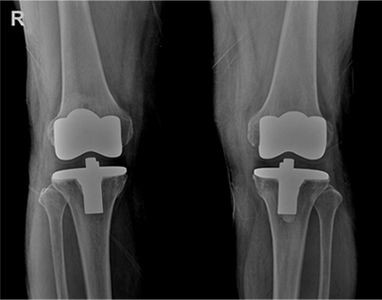

새통영병원은 환자의 상태에 따라 맞춤형 인공관절 치환술을 합니다.

( 인공관절 부분 치환술, 인공관절 전 치환술, 맞춤형 인공관절 치환술)

전체 인공관절 치환술